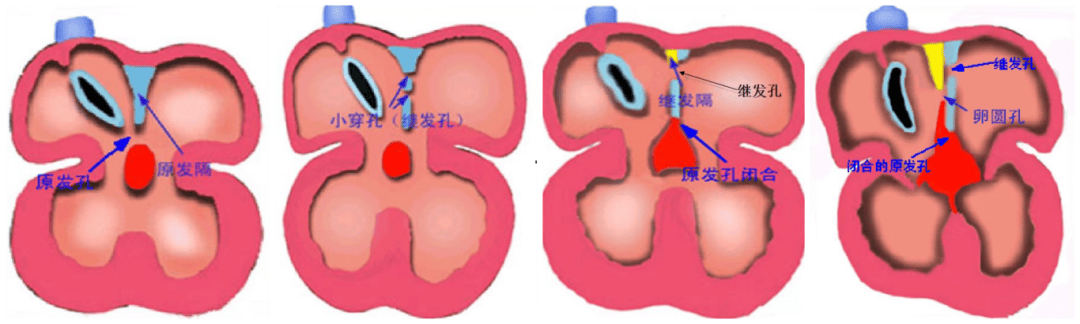

房間隔缺損(Atrial Septal Defect, ASD)是較常見的一種先天性心臟病,由于胚胎期房間隔發(fā)育、吸收或融合異常,導(dǎo)致左右心房之間殘留未閉的房間孔。房間隔缺損可單獨(dú)存在,或與其他心血管畸形合并存在。

房間隔缺損是由原發(fā)隔和繼發(fā)隔組成,原發(fā)隔位于左側(cè),繼發(fā)隔位于右側(cè)。

房間隔缺損分原發(fā)孔型與繼發(fā)孔型,通常房缺是指繼發(fā)孔型。根據(jù)缺損部位不同分為四型:

中央型又稱卵圓窩型:位于房間隔中部相當(dāng)于卵圓窩部位,此型最常見,76%;

下腔型:缺損位于房間隔后下方,與下腔靜脈入口相延續(xù),12%;

上腔型:位于房間隔后上方,缺損與上腔靜脈入口無明確界限,3.5%;

混合型:兼有上述兩種以上的巨大房間隔缺損,8.5%。